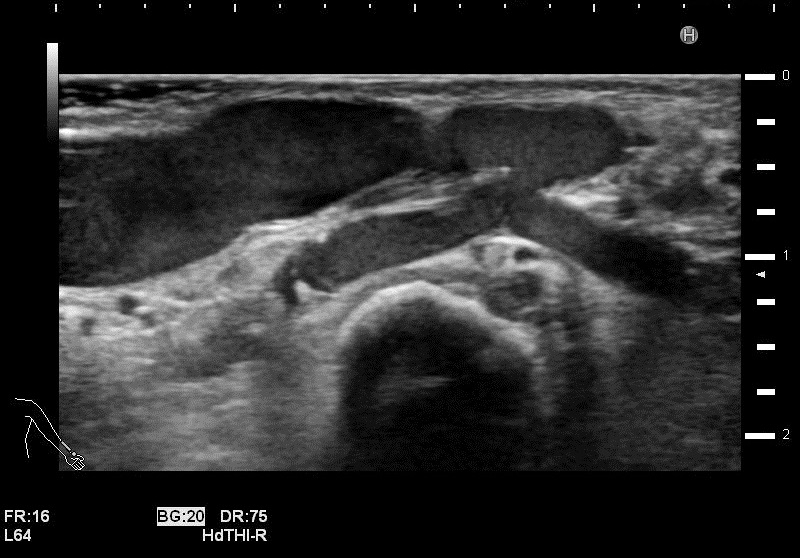

吻合部画像

・吻合部の観察

吻合形態や、石灰化の有無、狭窄等を観察しています。